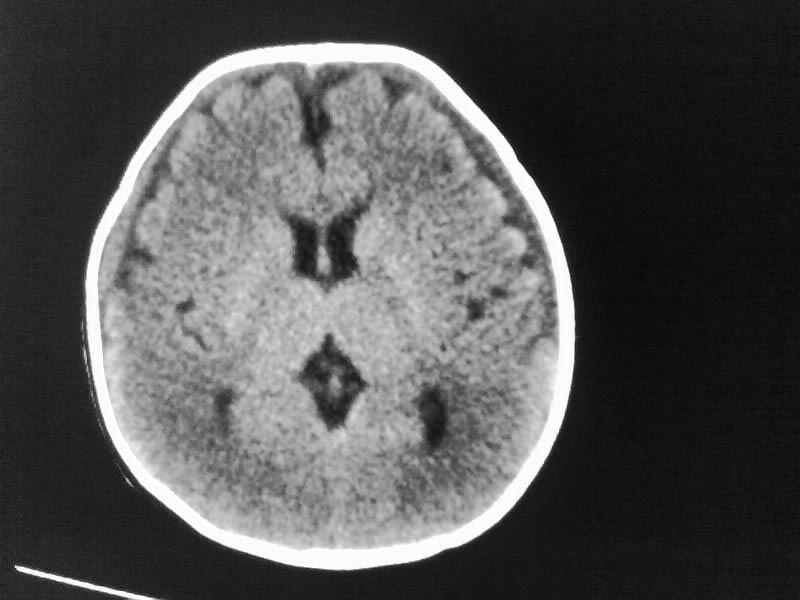

以下是引用小初学者在2009-4-15 10:26:00的发言:[br]考虑右侧额顶部硬膜下血肿。

以下是引用随光逐影在2009-4-15 17:59:00的发言:[br]1)右侧额颞顶部硬膜下血肿。2)外部性脑积水。